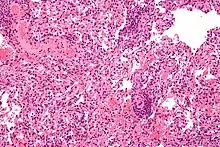

Micrograph showing lung transplant rejection. Lung biopsy. H&E stain.